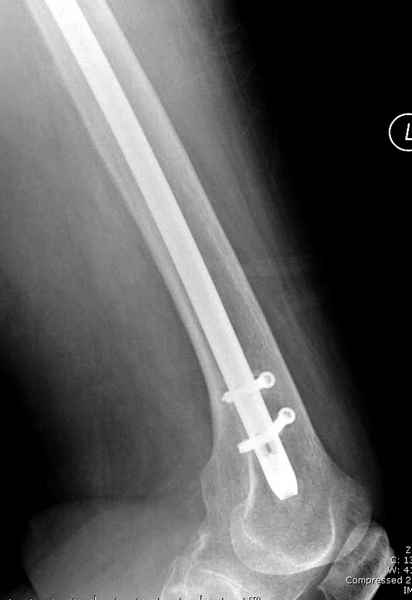

Михаил, здравствуйте. Если присмотреться - на четвертом снимке есть перелом гвоздя по отверстию.

Видимо, проблем тут две: во-1-х, центральный отломок был оставлен в варусно-сгибательной установке, во-2-х, не динамизировали вовремя.

Нижние винты хотели сломаться, но, увы, один не сломался, и тогда сломался гвоздь. Хотя и при динамизации в таком положении отломков

могло не срастись.